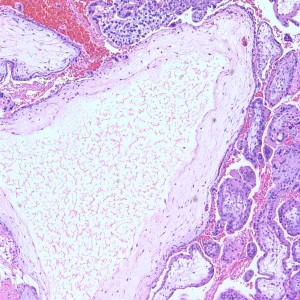

Diagnosis: Placental site nodule with scant strips of inactive endometrium.

The biopsy contains rare areas like this with scan strips of surface tubal and lower uterine segment epithelium, but without any real appreciable glandular tissue.

However, in one field we see a well-circumscribed nodule that, on low power, is very pink and glassy appearing, with large cells admixed.